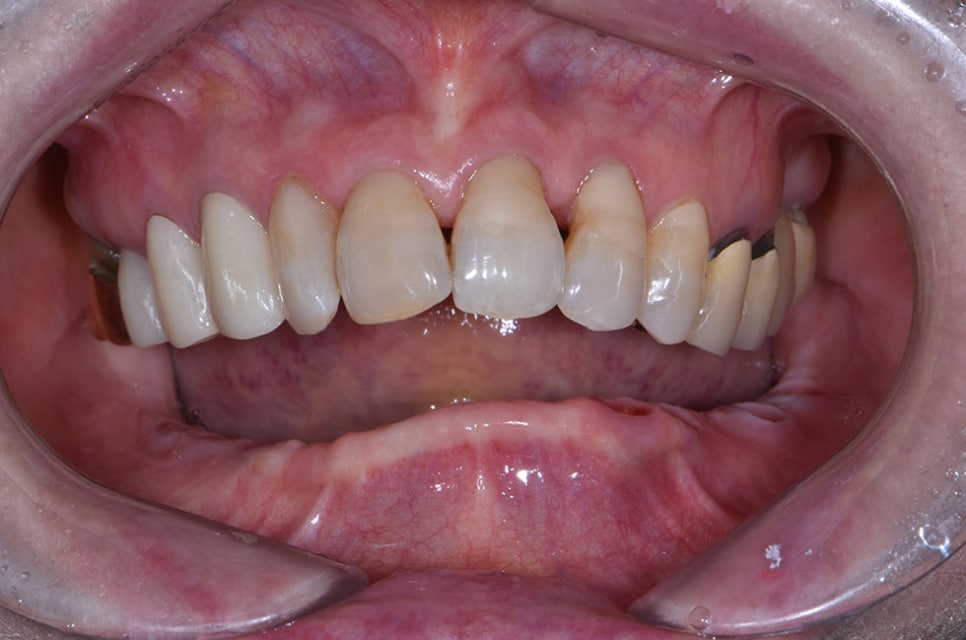

위에 사진과 같이 다수의 치아를 상실한 경우,

치아 전체를 임플란트로 대체하는

전체 임플란트 치료를 받아야 하는데요.

일반적인 임플란트 치료에 비해

교합의 안정성과 숙련된 경험이 요구되는

치료로 난이도가 높기 때문에 명확하고

꼼꼼한 치료를 위해 강남임플란트잘하는치과

본 의료진의 역량이 요구될 수 있습니다.